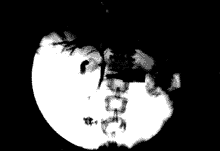

(3)胆道内支架植入术沿导丝送入胆道内支架输送器及胆道内支架,定位在狭窄段,位置确定后释放内支架,观察支架展开情况,若展开不良再用球囊导管扩张内支架使其充分展开。之后行胆道造影,观察胆道内支架是否通畅(如图1,2)。

图1 病人,女,39岁,胰腺癌梗阻性黄疸PTC示:肝内胆管扩张,肝管、胆总管闭塞

图2 胆管支架置入后,肝内胆管扩张消失,肝管、胆总管通畅,十二指肠显影。

(前头所指为支架)